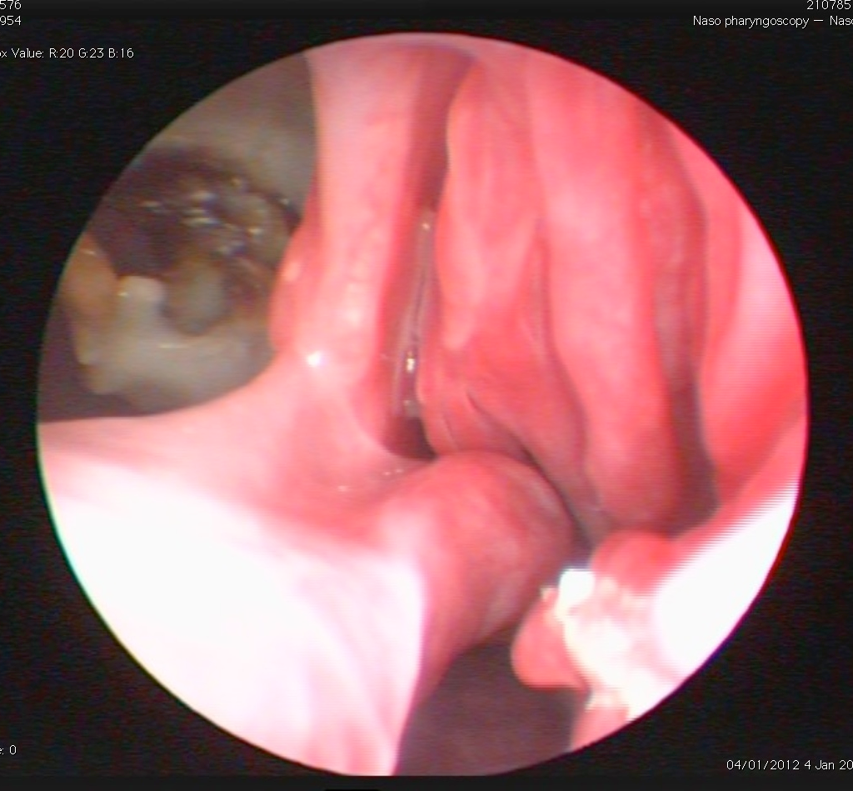

What is the probem here?

Destruction and white plaques – usually Aspergillus

The rhinoscope usually follows the path quite easily